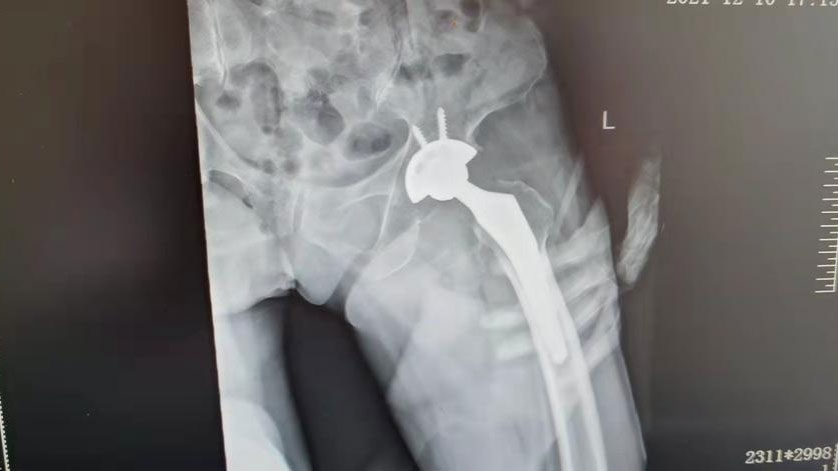

术后复查图片

3月17日,州骨科专家骆渊城副院长主刀,在骨伤科、麻醉科及手术室团队的通力协作下,顺利为吴婆婆实施了手术。手术非常成功,吴婆婆在手术后第二天就可以在步行器的辅助下行走了。自今年2月以来,我科在来凤县首次独立开展侧卧位直接前侧入路(DAA)微创髋关节置换术以来,已开展多例,效果满意。